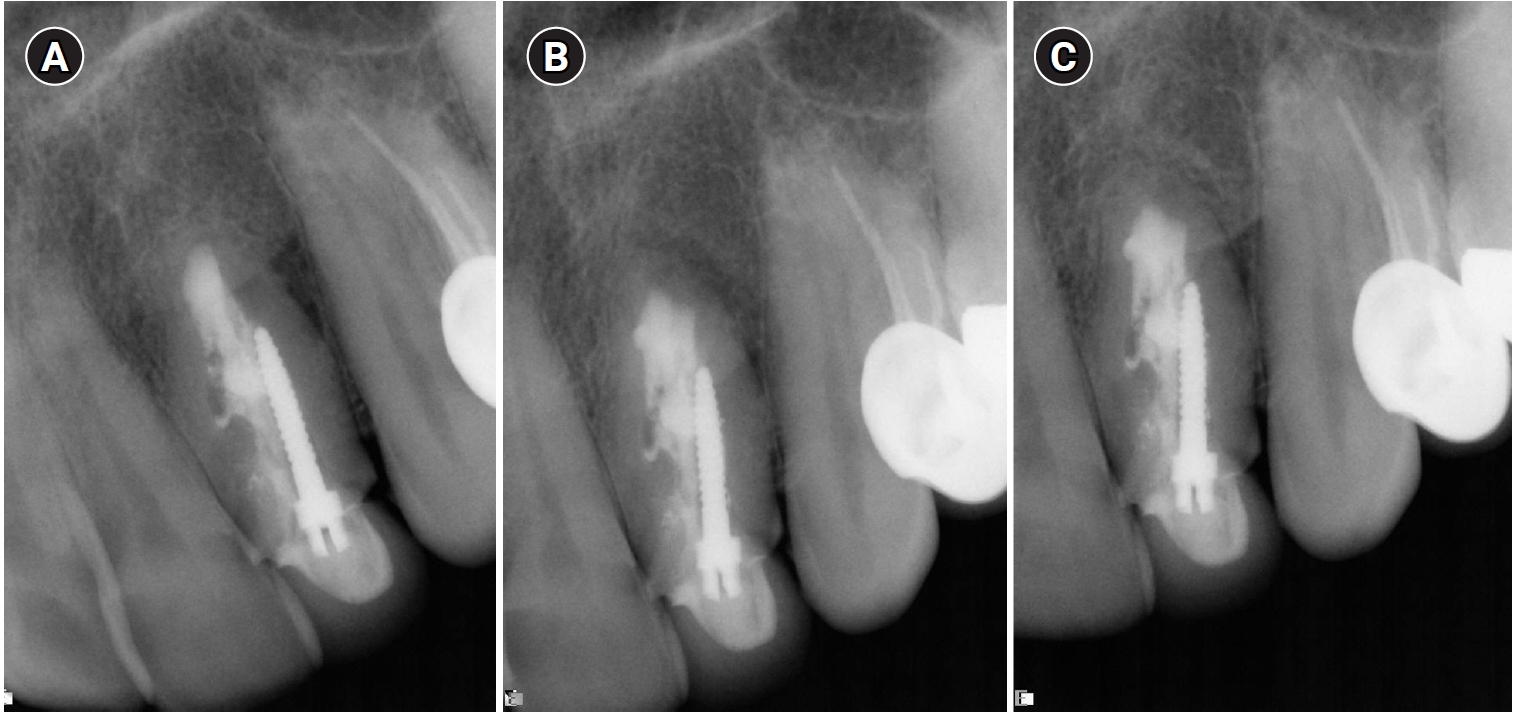

In 2011, 9 years later, the patient came back with a complaint of sensitivity in the area and purulent exudate. Clinically, the tooth was sensitive to percussion and palpation in the periapical area with signs of a sinus tract in the buccal apical area. A diagnosis of chronic apical abscess was made. A second endodontic surgery used the same technique as the previous treatment, taking care to minimize the apical resection in order not to compromise the crown-root ratio. Two years following the second surgery, the tooth was asymptomatic and completely healed radiographically (Figure 3).